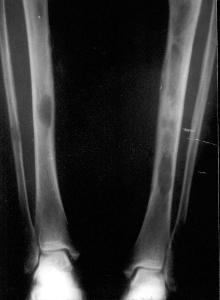

• 诊断骨炎,主要依据X线检查和病理组织学检查。

• X线检查

• X线检查可显示早期和晚期骨质改变,为诊断提供依据。

• X线片可见靠近关节面处的髂骨皮质出现硬化性改变,骨质呈致密状,位于骶髂关节下1/2处,且多呈三角形;骶髂关节间隙整齐、清晰,关节面及骨质无破坏征。畸形性骨炎可见长骨弯曲畸形,骨骼增粗,密度增高,骨小梁增多增粗。